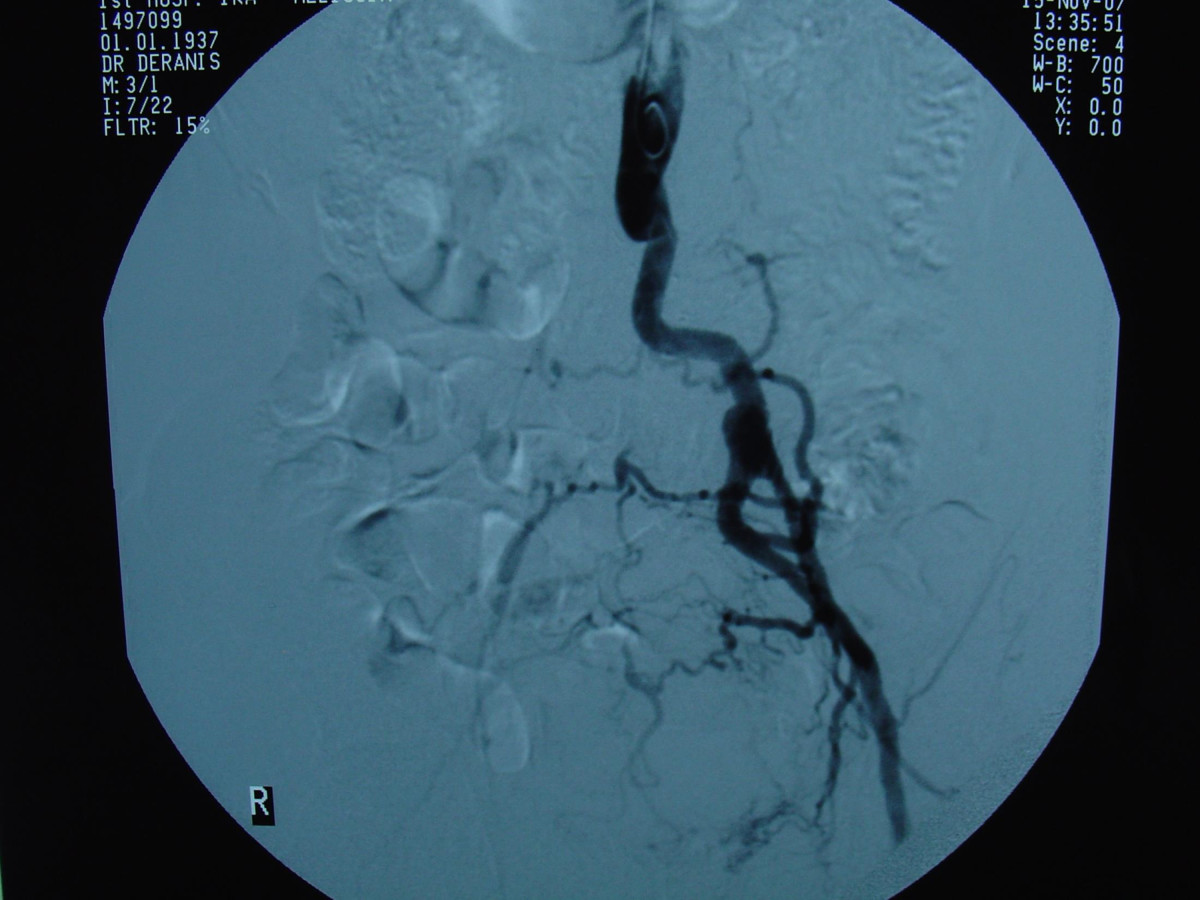

Endovascular repair of anastomotic abdominal aortic aneurysm, after aortobifemoral bypass

Vascular Clinic, Naval and Veterans Hospital of Athens

AVEM2009-Thessaloniki